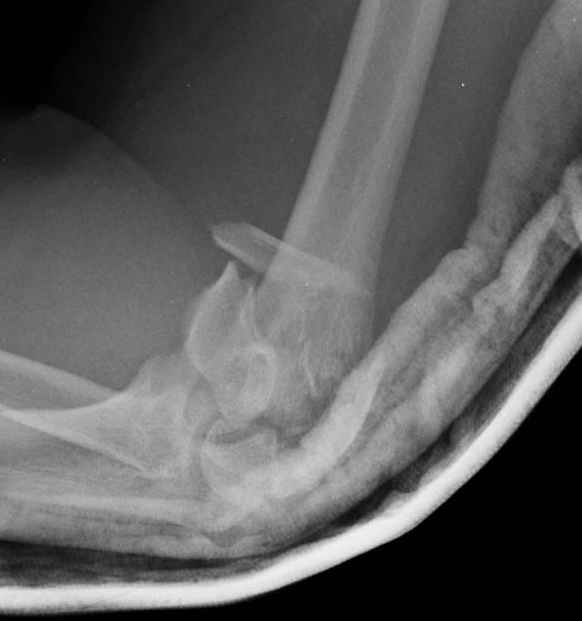

Примерный случай, только перелом был открытый, в задне-медиальной стороне рана около 2 см по характеру "изнутри кнаружи", неврологический статус со слабостью сгибания мизинца, также слабая абдукция и аддукция указательного пальца и сгибания в кисти.

Больному сделали обработку и наложили временный аппарат внешной фиксации плечо-предплечье.

На шестой день сделали открытую репозицию чрезлоктевым доступом двумя locking plate, локтевой нерв был ушибленным, после операции положительная динамика в Flexor Carpi Ulnaris. Фиксацию локтевого отростка произвели tension band technique с дополнительным шурупом.

Этапы операции на снимках....